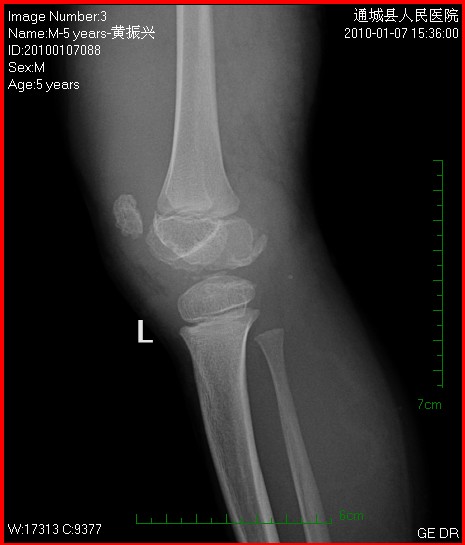

以下是引用随光逐影在2010-1-9 8:21:00的发言:[br]考虑左侧大、小腿外侧软组织内蔓状血管瘤伴左膝关节侵蚀,左侧髌骨及左侧股骨下端、胫骨上端骨骺异常发育。

以下是引用zxl51642在2010-1-9 17:29:00的发言:[br]首先要排除外敷药物等伪影,软组织血管瘤彩超没看见?[br]关节面凸凹不平,软骨及软骨下骨坏死,股骨内髁下方见碎骨片影,可能:1、首先考虑幼年型类风湿;2、股骨髁缺血性坏死,原因可能类似blount';s病机理;3、男性患儿查个尿排除尿黑酸症。